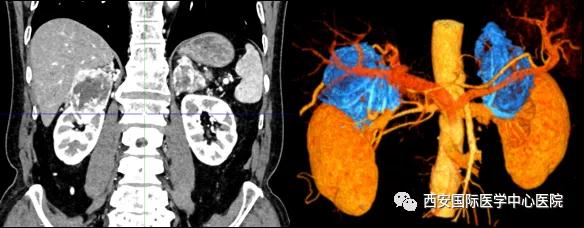

今年七十五歲的患者,來自陜西省商洛市,四月前因腰背部疼痛就診于當(dāng)?shù)蒯t(yī)院,行CT檢查發(fā)現(xiàn)“右腎、雙側(cè)腎上腺占位,前縱膈淋巴結(jié)腫大,雙肺多發(fā)結(jié)節(jié)、胸椎骨質(zhì)破壞,考慮轉(zhuǎn)移瘤”。為進(jìn)一步診斷治療,患者的兒子帶他來到西安某三甲醫(yī)院,查泌尿系CT提示“右腎占位性病變,多考慮腎癌,雙側(cè)腎上腺多發(fā)轉(zhuǎn)移灶,腹膜后多發(fā)腫大淋巴結(jié)”;行穿刺活檢提示“腎透明細(xì)胞癌”;并給予患者口服靶向藥物的治療方案。

自四月份至今,患者一直口服靶向藥物治療(阿昔替尼5mg 2次/日),期間無不良反應(yīng),目前腰背部疼痛癥狀也有所緩解,復(fù)查影像學(xué)資料提示瘤體較前縮小,腫瘤完整切除的可能性明顯提高;而且患者的兒子也是一名外科醫(yī)生,所以他更想為父親完成后續(xù)的手術(shù)治療。

手術(shù)由楊增悅教授主持,舒濤主治醫(yī)師、王東主治醫(yī)師主刀,黃怡醫(yī)師、王平醫(yī)師協(xié)助完成。由于第四代達(dá)芬奇機(jī)器人更加靈活和精準(zhǔn)的特性,手術(shù)全程順利,尤其是完全精準(zhǔn)的“解鎖”了右腎動(dòng)脈和右腎靜脈的數(shù)十根交互纏繞的分支血管。術(shù)后患者麻醉恢復(fù)后生命體征平穩(wěn),順利返回泌尿外科普通病區(qū)進(jìn)一步康復(fù)。